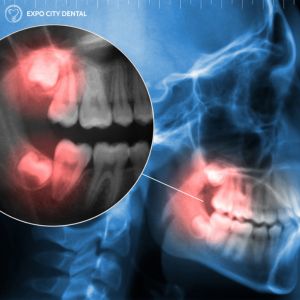

Some approximations estimate that about 85% of Canadian adults will have had a wisdom tooth extraction at some point during their life. From managing pain and preventing infection to reducing the chances of changes in your bite, there are a number of reasons why dentists in Vaughan will recommend you undergo wisdom teeth removal procedures. Removal is typically an option when the molars are erupting and causing severe pain, discomfort, or infection, or if the tooth is impacted. At Expo City Dental, we provide comprehensive wisdom teeth removal in Vaughan, so patients can be relieved of the pain, discomfort, and debilitation of impacted wisdom teeth.

The average adolescent or adult dealing with impacted wisdom teeth may not realize it, as the tooth would not be visible, so it’s helpful to know the signs that you should book a visit or consultation with your dentist. Here are some of the signs it’s time to talk to your local dentist at Expo City Dental about impacted wisdom teeth removal.